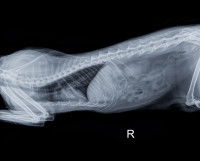

Divers examens permettent d'établir un diagnostic fiable de l’asthme du chat et d'en déterminer la sévérité :

En l'absence de lésions dans l'appareil respiratoire, l'asthme félin n'est pas toujours facile à diagnostiquer, car ses symptômes ressemblent à ceux d'autres maladies respiratoires.

Le vétérinaire procède donc généralement à des examens complémentaires dans le but d'éliminer les autres hypothèses, c'est-à-dire les autres infections possibles : c'est ce qu'on appelle un diagnostic différentiel.